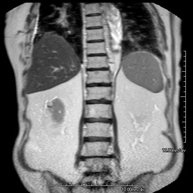

- RM d'Abdomen

Prova diagnòstica no invasiva que consisteix en l'obtenció d'imatges d'alta definició anatòmica de l'abdomen mitjançant l'ús d'un camp electromagnètic i ones de ràdio (amb un emissor i un receptor). No utilitza radiació ionitzant. En aquesta exploració s'inclouen el fetge, el pàncrees, la melsa, la via biliar, la vesícula biliar, les glàndules suprarenals, els ronyons, l'aorta abdominal, la vena cava inferior, l'estómac, el duodè, etc. En alguns casos caldrà emprar contrast paramagnètic (Gadolini) per caracteritzar les lesions. - RM Pelvis femenina

Prova diagnòstica no invasiva que consisteix en l'obtenció d'imatges d'alta definició anatòmica del fetge mitjançant l'ús d'un camp electromagnètic i ones de ràdio (amb un emissor i un receptor). No utilitza radiació ionitzant. Es realitza per estudiar qualsevol lesió localitzada en el fetge. Normalment es requereix l'ús de contrast paramagnètic (Gadolini) per caracteritzar les lesions. És necessari realitzat la prova en dejú (6 hores). - RM de Ronyons

Prova diagnòstica no invasiva que consisteix en l'obtenció d'imatges d'alta definició anatòmica d'ambdós ronyons mitjançant l'ús d'un camp electromagnètic i ones de ràdio (amb un emissor i un receptor). No utilitza radiació ionitzant. Es realitza per estudiar qualsevol lesió localitzada en ambdós ronyons. Normalment es requereix l'ús de contrast paramagnètic (Gadolini) per caracteritzar les lesions. - RM de Glàndules Suprarenals